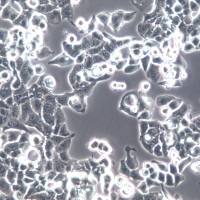

- 细胞形态:

贴壁;多角形

- 生长状态:

贴壁;上皮细胞样

NCI-H157细胞系、NCI-H157细胞、NCI-H157非小细胞肺腺癌细胞